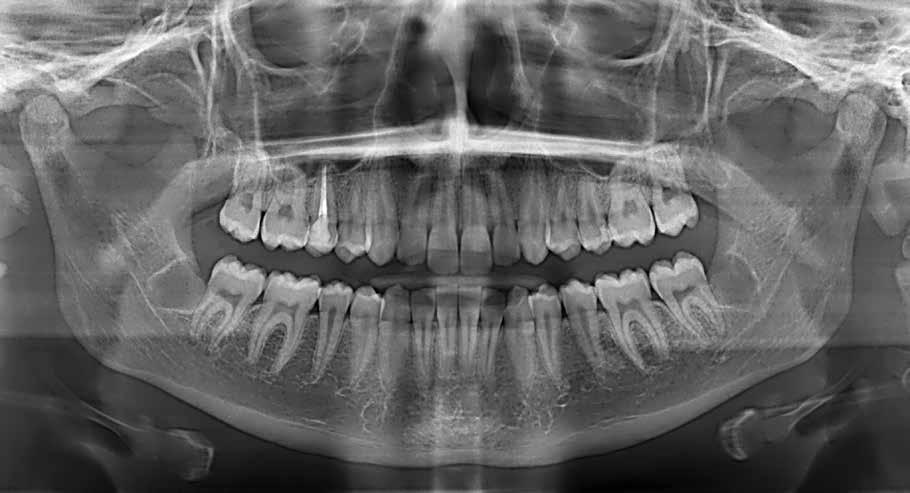

47 46 ESTETICA FUNZIONE POSTURA Valori cefalometrici a 10 anni : ANB ANB 2.70 Posizione del Mascellare SNA 78,70 Posizione della Mandibola SNB 76.0 Angolo Articolare SArGo 142,76 Angolo Goniaco ArGoMe 125,73 Angolo incisivo inf^Corpo madibolare IiMand 92,00 Angolo incisivo Sup^Base Cranica Ant. IsCran 96,00 Angolo Interincisivo II 130,0 53 _ Esame Cefalometrico a dieci anni. 54 _ Tabella dei valori cefalometrici a dieci anni. 55 _ Ortopantomografia di controllo a dieci anni. 56 _ Teleradiografia di controllo con evidente stabilità del caso dal punto di vista scheletrico/posturale.

Presentazione del caso > F.V, bambino di cinque anni, presenta una malocclusione di II Classe scheletrica, III Classe dentale molare e canina destra e sinistra, morso inverso anteriore. Le arcate dentali mostrano usura degli elementi dentari anteriori a causa dell’occlusione patologica. Le linee mediane, superiore ed inferiore, sono centrate; il frenulo labiale superiore patologico per un’eccessiva estensione inter-incisale.

Il piano di trattamento prevede l’utilizzo di un dispositivo elastodontico di III Classe, da portare per due ore diurne e tutte le notti in modo passivo, senza effettuare alcun esercizio, al fine di ripristinare una relazione molare e canina bilaterale di I Classe ed il corretto avanzamento maxillare e inibire l’eccessiva crescita mandibolare. È possibile ottenere il risultato in pochissimi mesi di terapia, essendo la crescita del paziente molto attiva.

In un secondo momento, alla risoluzione della problematica scheletrica, si monitorizzerà il caso con visite semestrali in modo da reintervenire qualora si dovesse ripresentare la problematica.

Dall’esame clinico si evince la III Classe dentale, l’inversione anteriore e l’over-jet negativo.

Una volta ottenuta la correzione del rapporto molare ed incisale, l’apparecchio elastodontico verrà portato dal paziente solo durante la notte per stabilizzare il risultato ottenuto e guidare l’eruzione degli elementi dentari per un totale di quattordici mesi di terapia. ad inizio trattamento :

ANB ANB 4,8 Posizione del Mascellare SNA 92.2

Posizione della Mandibola SNB 87,44 Angolo Articolare SArGo 153,00 Angolo Goniaco ArGoMe 118,00 Angolo incisivo inf^Corpo madibolare IiMand 75,00 Angolo incisivo Sup^Base Cranica Ant. IsCran 107,05 Angolo Interincisivo II 144,40 59

Ortopantomografia iniziale. 60 _ Tracciato cefalometrico ad inizio terapia. 61 _ Valori cefalometrici ad inizio terapia.

Considerazioni > L’analisi cefalometrica ad inizio trattamento dimostra la II Classe scheletrica con protrusione del mascellare superiore e prognazia mandibolare; tendenza alla crescita verticale. L’esame clinico evidenzia una protrusione mandibolare funzionale.